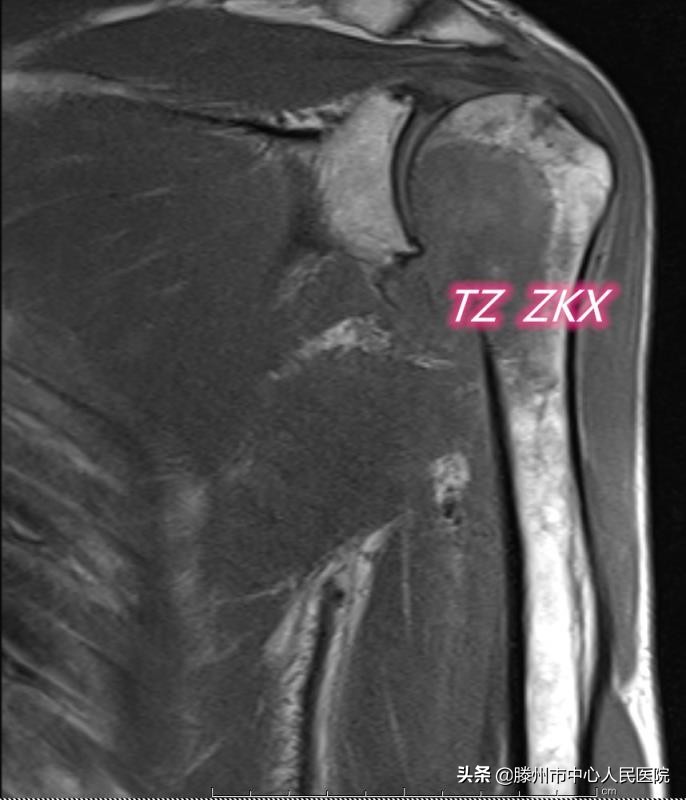

患者71岁,2019年12月诊断胃底-贲门癌并纵膈、腹膜后淋巴结多发性转移,经过6个周期药物治疗,病情稳定。3月前出现左侧肩胛部疼痛,逐渐加重,上肢活动受限,CT及MRI显示左侧肱骨头及肱骨上段溶骨性转移,骨皮质破坏范围超过1/2,随时都有发生病理性骨折的可能,一旦发生病理性骨折,必将严重影响患者的生活质量。骨科会诊考虑患者高龄,伴有其他多部位转移,不适合手术治疗,建议微创治疗。张开贤主任医师团队在借鉴既往多年骨转移瘤微创治疗经验的基础上,经过多次讨论,决定实施CT引导微波消融联合介入内固定及骨水泥成形术。

8月11日,张开贤主任医师团队在麻醉科的协助下,采用臂丛麻醉,在CT引导下经皮穿刺,首先对病变区域进行微波消融,利用高温使肿瘤发生凝固性坏死,然后在肱骨髓腔内置入两根克氏针,最后注射骨水泥,使克氏针、骨水泥与肱骨融合在一起,从而起到杀灭肿瘤、缓解疼痛、增加骨骼的稳定性、预防病理性骨折的作用。